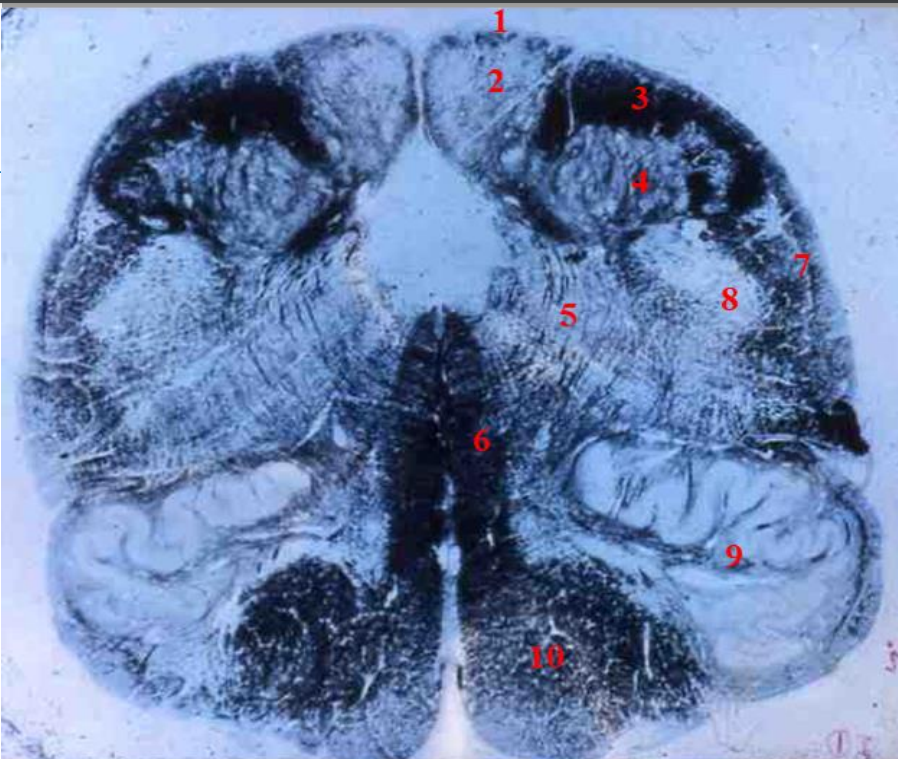

4

5

Perfectly

Q

3

A